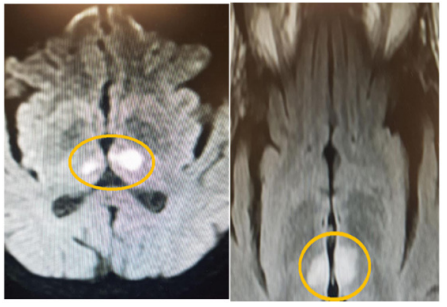

A 42-year-old female is admitted to hospital with a lower level of consciousness. Toxic-metabolic causes were excluded, orotracheal intubation measures were taken and sent to the Intensive Care Unit (ICU), but there is no return to the level of consciousness.1,2 Computed tomography image examinations were performed, revealing hypodensity in thalamic regions, and then magnetic resonance imaging, showing an infarction area in thalamic regions bilaterally. She spent 15 days in the Intensive Care Unit, progressing with a worsening of the general condition, pneumonia and dying from sepsis.3

The main symptoms resulting from infarction due to AOP occlusion are changes in the level of consciousness such as disorientation, confusion and hypersolence, in addition to deep coma, akinetic mutism, amnesic syndrome, dysarthria and aphasic disorders, hypophonia and dysprosia, vertical gaze paralysis. Imaging exams are extremely important in diagnosis. Computed Tomography (CT) and angioCT images can be useful to detect bitalamic infarction; however, to determine its etiology, Magnetic Resonance Imaging demonstrates the type of vascular occlusion, in addition to providing the differential diagnosis with other relevant pathologies, mainly toxic-metabolic causes, such as carbon monoxide poisoning, Wenicke's encephalopathy and osmotic myelinolysis, and venous causes, such as the thalamus venous drainage thrombosis. The latter being an important distinction, as it requires different prognoses and other types of therapies.5,6

(Figure 1) Arterial bitalamic infarcts have high rates of morbidity and persistent deficits, with a worse prognosis when symmetrically affecting both thalamus. Unfortunately, these patients are rarely submitted to thrombolysis and adequate ventilatory support. Our report highlights the importance and need to make a quick diagnosis and intervention, especially in those patients who vary between unconscious and comatose states, as these infarctions are more severe and bring consequences that last for a lifetime or even lead to death. Recalling also the relevance of performing imaging tests for the distinction with other causes to institute appropriate therapy in a timely manner.